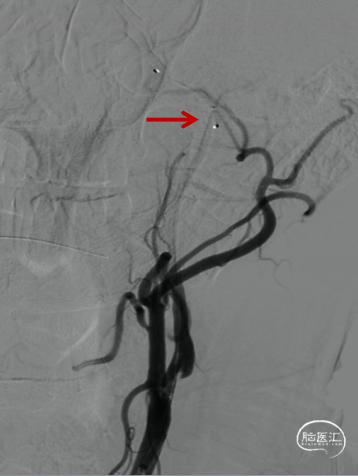

交换出微导管及多功能导管,C2段放置SPIDER保护伞后以3-30mm球囊和6F 115cm SKATHI远端通路导管采用球囊接力技术越过颈内动脉闭塞段,由下及上持续抽吸。

抽吸状态下整体撤出保护伞,继续抽吸,血栓堵塞SKATHI导管及导引导管,负压下整体将系统撤出,可见大量血栓。

微导管微导丝携SKATHI远端通路导管负压状态下再次进入颈内动脉,造影确认颈内动脉通畅,大脑中动脉中远段可见栓塞。